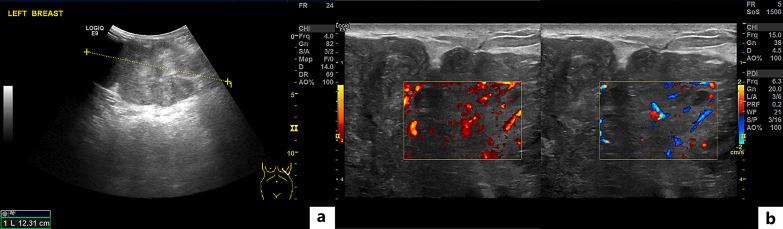

In this report, we describe the case of a 41-year-old woman, who presented with a rapid growth of a phyllodes tumor after an accidental bump on the breast and had to undergo mastectomy followed by breast reconstruction.

在本报告中,我们描述了一名41岁女性的病例,她在乳房意外碰撞后出现叶状肿瘤快速生长,不得不接受乳房切除术,随后进行乳房重建。